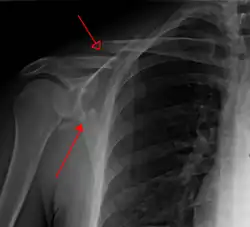

X-ray showing a fracture of the clavicula and scapula

Most fractures of the scapula can be seen on a chest X-ray; however, they may be missed during examination of the film.[1] Serious associated injuries may distract from the scapular injury,[4] and diagnosis is often delayed.[3] Computed tomography may also be used.[1] Scapular fractures can be detected in the standard chest and shoulder radiographs that are given to patients who have had significant physical trauma, but much of the scapula is hidden by the ribs on standard chest X-rays.[4] Therefore, if scapular injury is suspected, more specific images of the scapular area can be taken.[4]